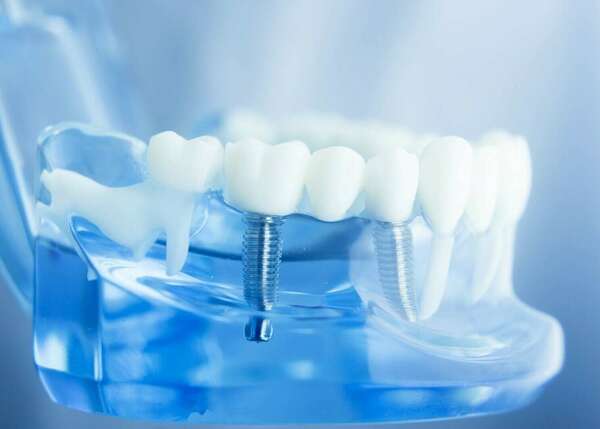

La mise en place des implants peut paraître impressionnante. Il s’agit pourtant d’une intervention assez rapide dont les suites se passent généralement bien.

Votre chirurgien-dentiste a identifié dans votre bouche une ou plusieurs dents absentes. Ces édentations sont la conséquence de déchaussements, de fractures ou d'infections. Dans tous les cas, il est impératif de les remplacer.